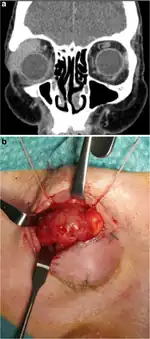

| Infiltrationat the level of the medium straight muscle of the LE which is shown in the axial NMR | |